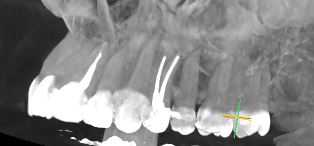

В начале июня возникла боль только при жевании нежесткой пищи в области 24 зуба. 12 июня после проведения предварительного холодового тестирования (реакции практически не было) была снята старая пломба, удален нерв, положено лекарство в каналы и поставлена временная пломба. Через 7 дней боль при жевании сохранялась, я старалась, чтобы пища не попадала на эту область. Боли в покое не было. Я говорила врачу, что болит при жевании по-прежнему, она начала пломбировать каналы и установила постоянную пломбу. Боль никуда так и не делась при жевании. 2 июля сделала КТ. 9 июля врач распломбировала 1 канал, положила туда лекарство, попросила с ней связаться через пару дней и обсудить самочувствие. Боль такая же при жевании, в покое тоже иногда что-то чувствуется. Болевой порог низкий, но не могу назвать ощущение в покое именно болью. Врач говорит о возможной трещине в зубе, вероятно она и дает боль при жевании, рекомендует диагностику на микроскопе, потому что трещины не всегда видны на КТ. Врач уточняет локализацию боли и подозревает, что болит, возможно, 25 зуб. Я кусаю ватную палочку перед зеркалом: при надкусывании палочки под 25 и 24 зубом боли нет, когда палочка находится под 23 и между 23 и 24 боль есть. Скажите, пожалуйста, может ли воспаление или иные проблемы в 24 зубе отдавать в 23?